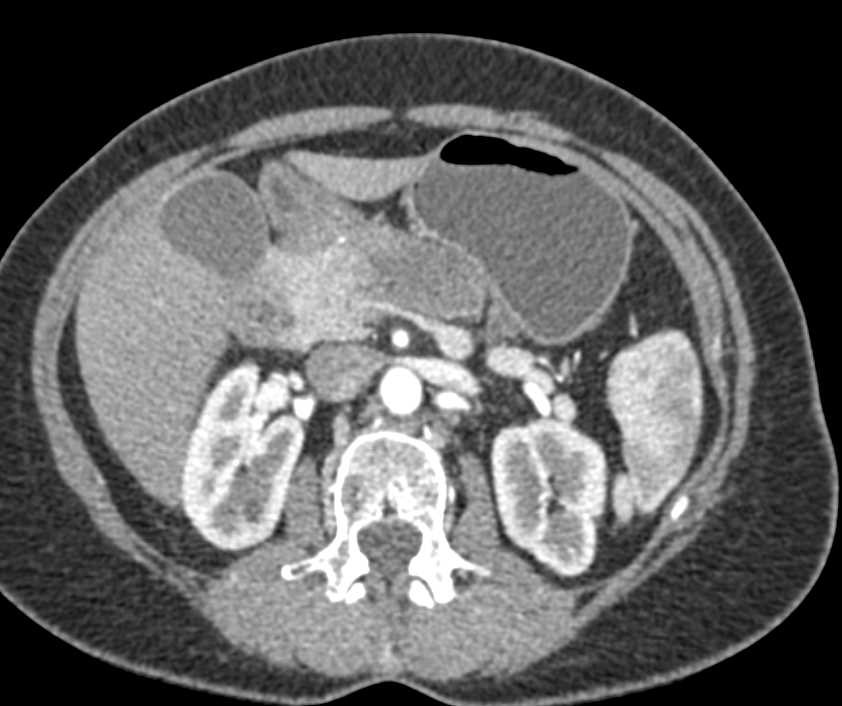

Acute Pancreatitis